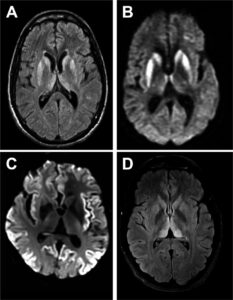

CJD profiles of MRI and EEG from probable CJD patient.

FLAIR-MRI of Creutzfeldt–Jakob disease.

- CJD_profiles_of_MRI_and_EEG_from_probable_CJD_patient © Bo-Yeong Choi1 , Su Yeon Kim1 , So-Young Seo1 , Seong Soo A An2 , SangYun Kim3 , Sang-Eun Park4 , Seung-Han Lee5 , Yun-Ju Choi5 , Sang-Jin Kim6 , Chi-Kyeong Kim1 , Jun-Sun Park1 and Young-Ran Ju is licensed under a CC BY (Attribution) license